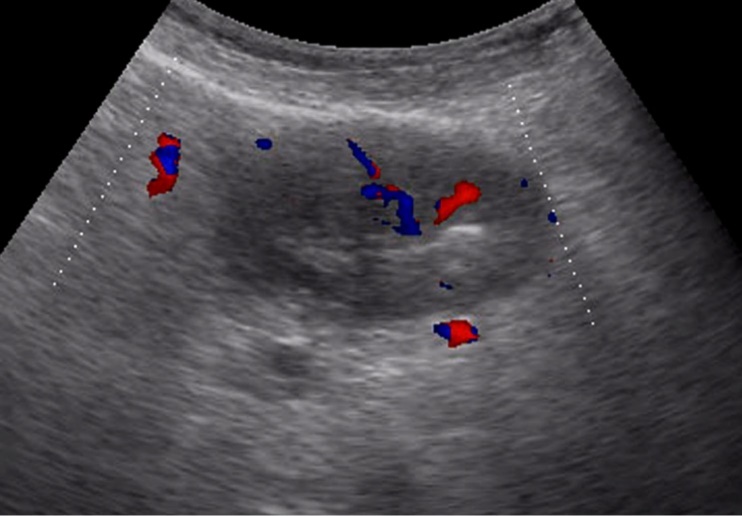

Weak vascularization was manifested in the form of a single point color vascular signals, the moderate vascularization - in the form of linear color vascular signals and the enhanced vascularization - in the form of wide color areas inside the tumor (Figure 16, Figure 17).

Figure 17.Gastric carcinomas of infiltrative ulcerative form of Ts stage. Despite the small size of the tumor the vascularization is manifested in the form of wide color areas inside the tumor.

Metastasis to the regional lymph nodes was diagnosed in 52 cases. Ultrasonographically, this was detected in 37 (71.2%) cases. Sonographic features of lymph node metastatic lesions are: an increase in their thickness, a decrease in echogenicity, deterioration or lack of differentiation of the peripheral and central parts of the nodes, recording of color vascular signals inside the nodes (Figure 18, Figure 19).

Figure 18.Metastasis to the retroperitoneal lymph node in gastric cancer of the antrum of T3 stage. The longitudinal size of the lymph node is increased to 5 cm, the echo is significantly reduced, along the periphery of it is visible color vascular signals in tissue Doppler mode.

Figure 19.Metastatic affected lymph node in gastric cancer of the anterior wall of the stomach of stage T4. Significantly enlarged lymph node, echogenicity reduced, large vascular signals in color Doppler mode visible in the center.